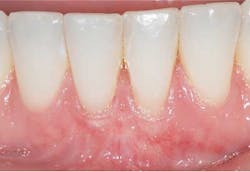

Preop: Alloderm (acellular dermal matrix), Emdogain, Coronally Advanced Flap (Tunneling Procedure)

Postop: Nine-month reevaluation